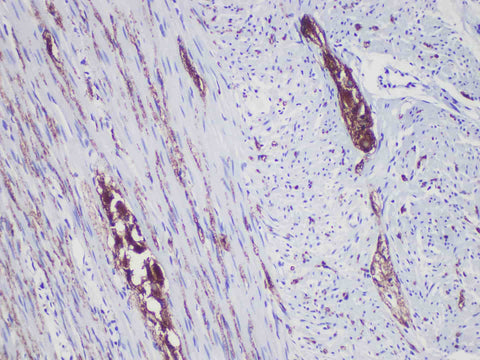

Synaptophysin(Syn) Monoclonal Antibody Stored at 2~8°C

Applications IHC-P

synaptophysin (Syn), also known as the major synaptic vesicular protein p38, is a protein encoded by SYP gene in human. It interacts with the basic synaptic vesicles, but when inactivated experimentally in animals, they still express and function normally. Syn reacts with neuroendocrine cells in adrenal medulla, carotid artery, skin, pituitary gland, thyroid gland, lung, pancreas and gastrointestinal mucosa. synaptophysin (Syn) Monoclonal can recognize normal neuroendocrine cells and neuroendocrine tumors. SYN is not expressed together with other neural differential markers and can be used as a differential marker to judge tumor.